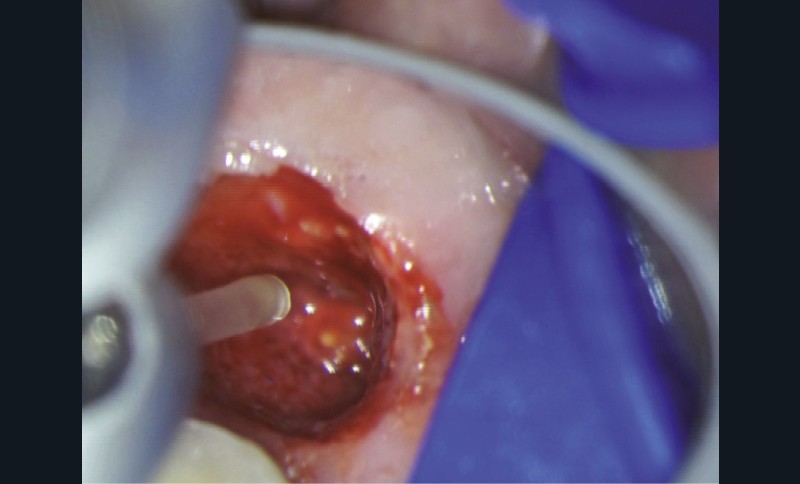

Le laser Er:YAG va permettre une élimination des débris en surface, une stérilisation, avec comme irrigation de l’eau stérile [36] et en coupant le spray, une hémostase avec la formation d’une couche de coagulation [37] propre à la formation d’un pont dentinaire au contact du biomatériau, qui peut être bio-actif, tel que la Biodentine (Septodont) (fig. 6a à d).

Protocole opératoire : sous anesthésie, une cavité suffisante à recevoir le biomatériau (2 à 3 mm) sous champ opératoire est réalisée. La désinfection au laser Er:YAG (40 mJ ; 20 Hz) sous spray, pendant 20 secondes, est alors mise en œuvre. S’en suit éventuellement une coagulation de 3 secondes, en coupant le spray, puis la mise en place du biomatériau Biodentine (Septodont). Il sera ensuite recouvert d’un matériau de restauration adéquate.